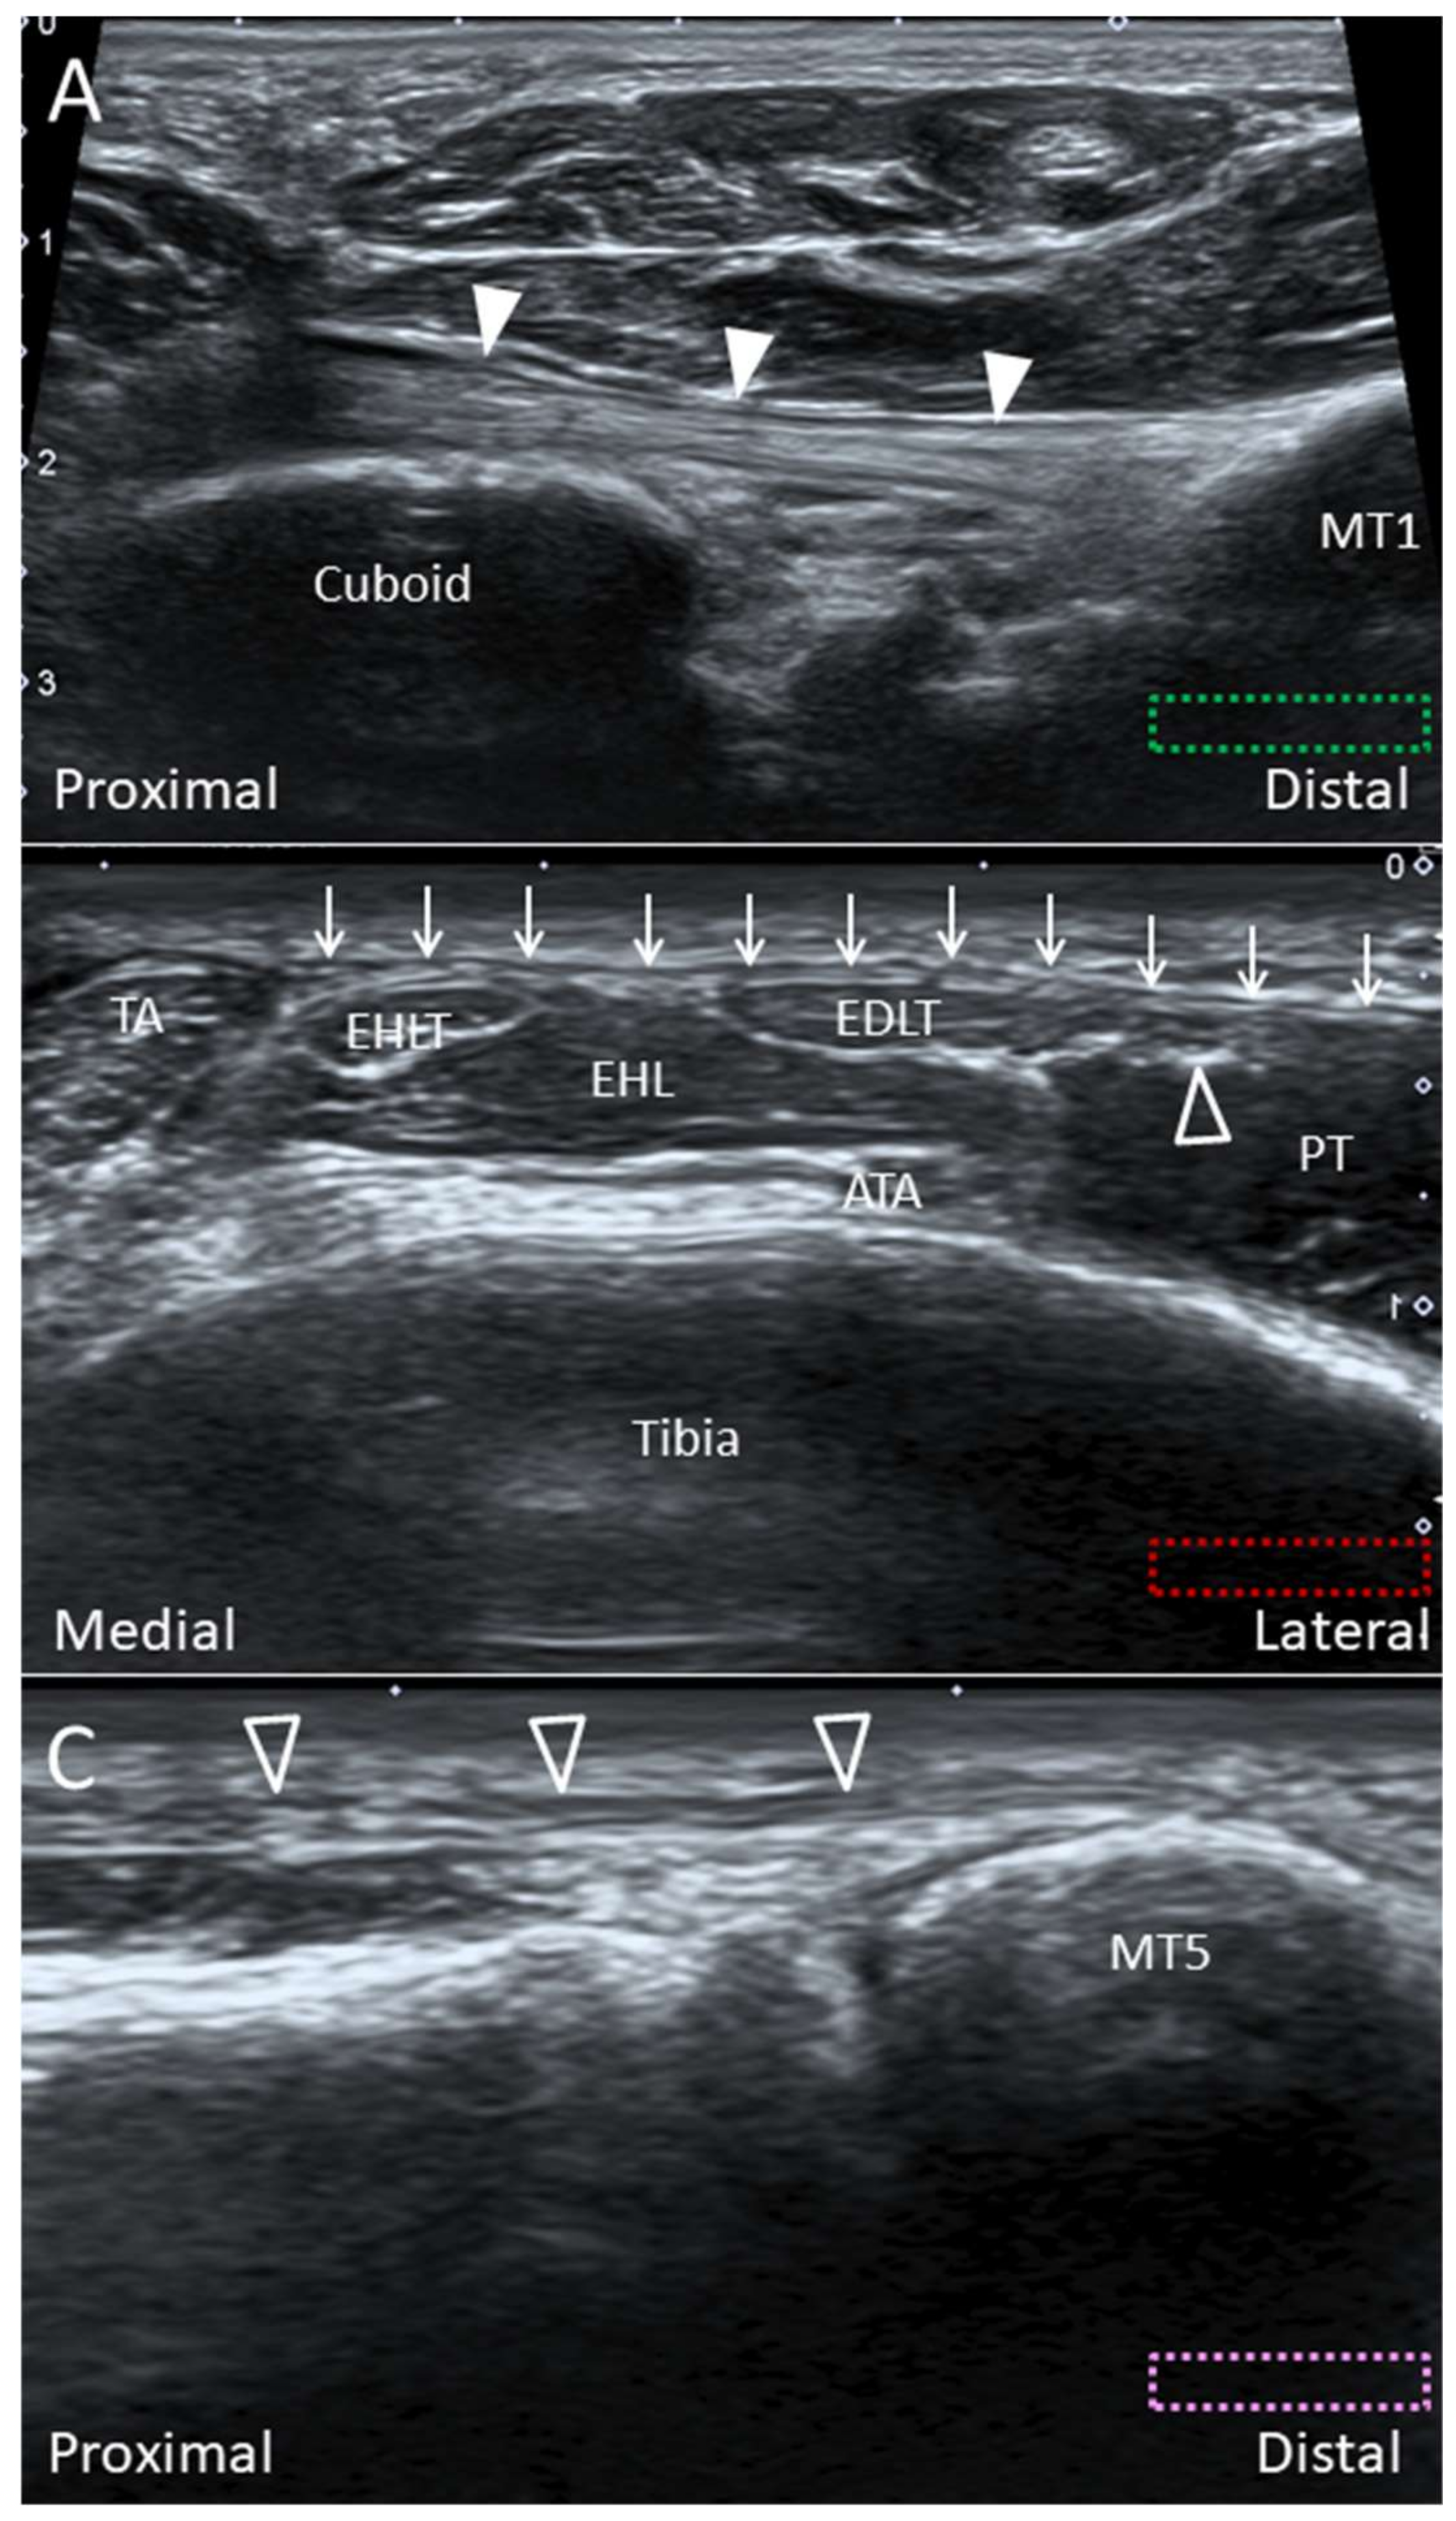

2.6. Bifurcate Ligament

2.6.1. Anatomy

2.6.2. Scanning Technique

2.6.3. Clinical Relevance

2.10. Lisfranc Ligament Complex

2.10.1. Anatomy

2.10.2. Scanning Technique

2.10.3. Clinical Relevance

2.11. Lateral Cord of the Plantar Fascia

2.11.1. Anatomy

2.11.2. Scanning Technique

2.11.3. Clinical Relevance

4.2. Peroneus Tertius Tendon

4.2.1. Anatomy

4.2.2. Scanning Technique

4.2.3. Clinical Relevance